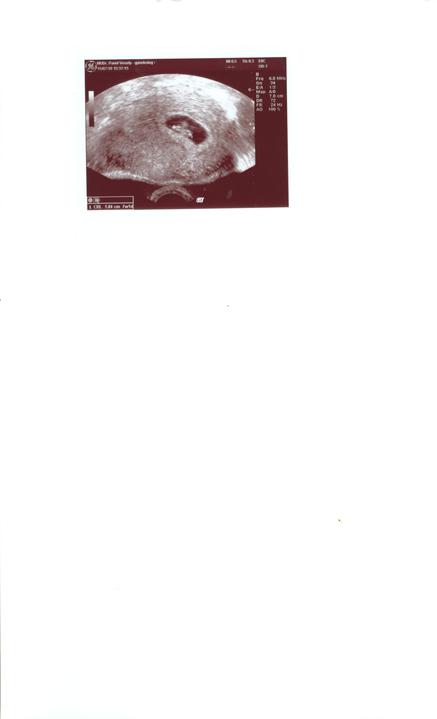

dnes som sa vratila z nemocnice, lebo v utorok ked som bola na kontrolnom sone koli velkosti babatka tak sme 2,5 tyzda pozadu, koli miernej poruche na prietokoch, v utorok idem na kontrolu tak hadam uz bude vsetko ok ...